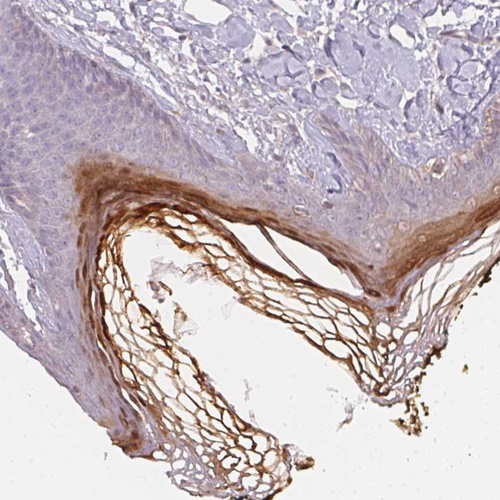

Immunohistochemistry analysis in human skin and liver tissues using HPA064307 antibody. Corresponding BLMH RNA-seq data are presented for the same tissues.